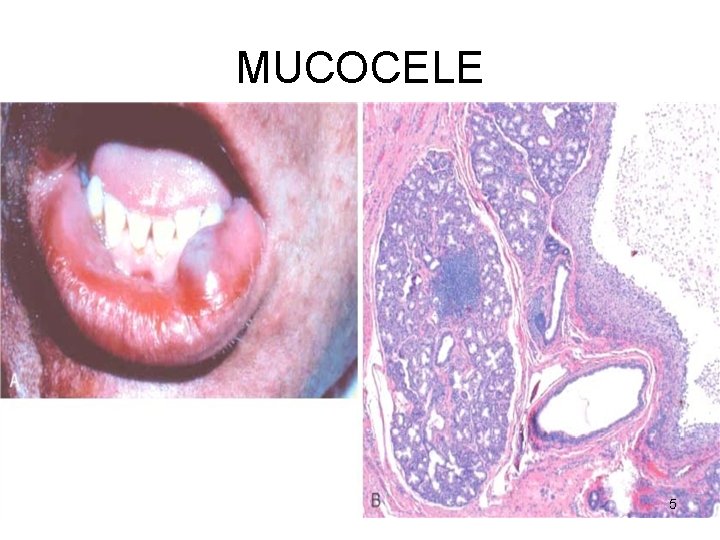

MUCOCELE • • Trauma Lower lip Fluctuant swelling Blockage / rupture of salivary duct → leakage of saliva into the surrounding stroma • RANULA – mucocele of the sublingual 4

MUCOCELE 5